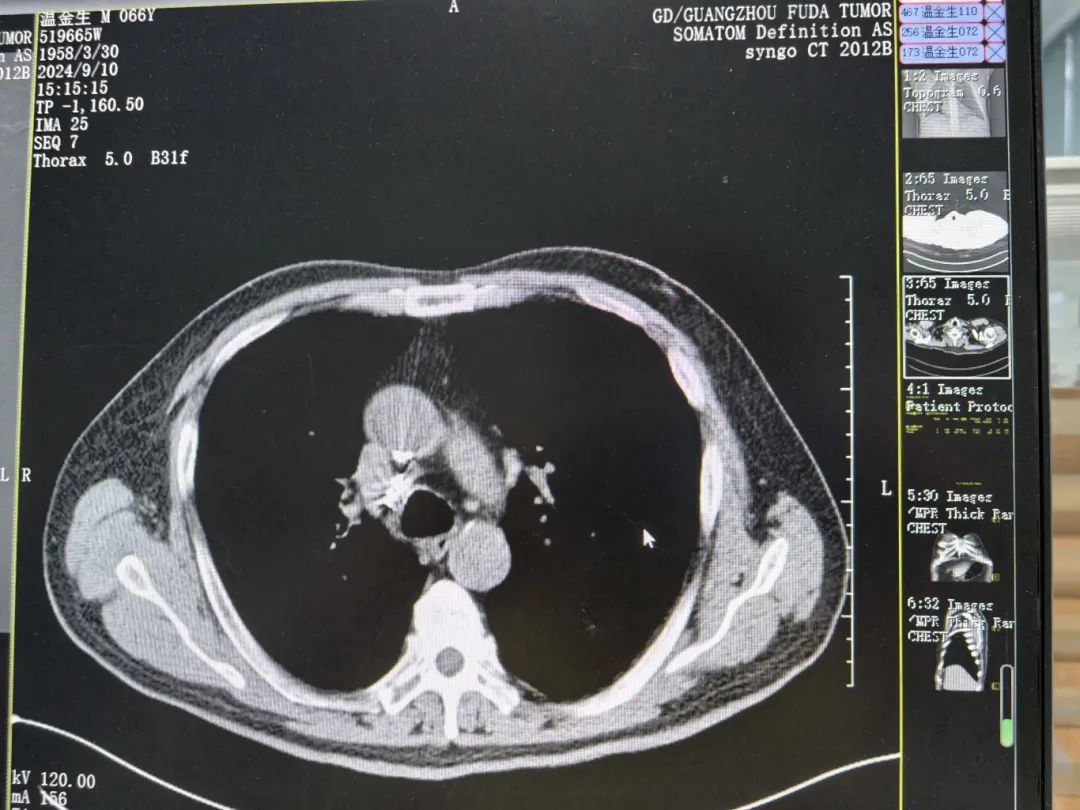

接受一次粒子植入以及三四次介入和免疫治疗后,金叔真心觉得当初的“直觉”是对的。一次次的疗程,一次比一次好,CT结果显示,金叔的右肺肺门区病灶明显缩小,纵膈部分肿大淋巴结以及双肺部分结节较前缩小。多次住院经历,让金叔在复大有了从未有过的良好就医体验。

▲治疗两月后影像结果